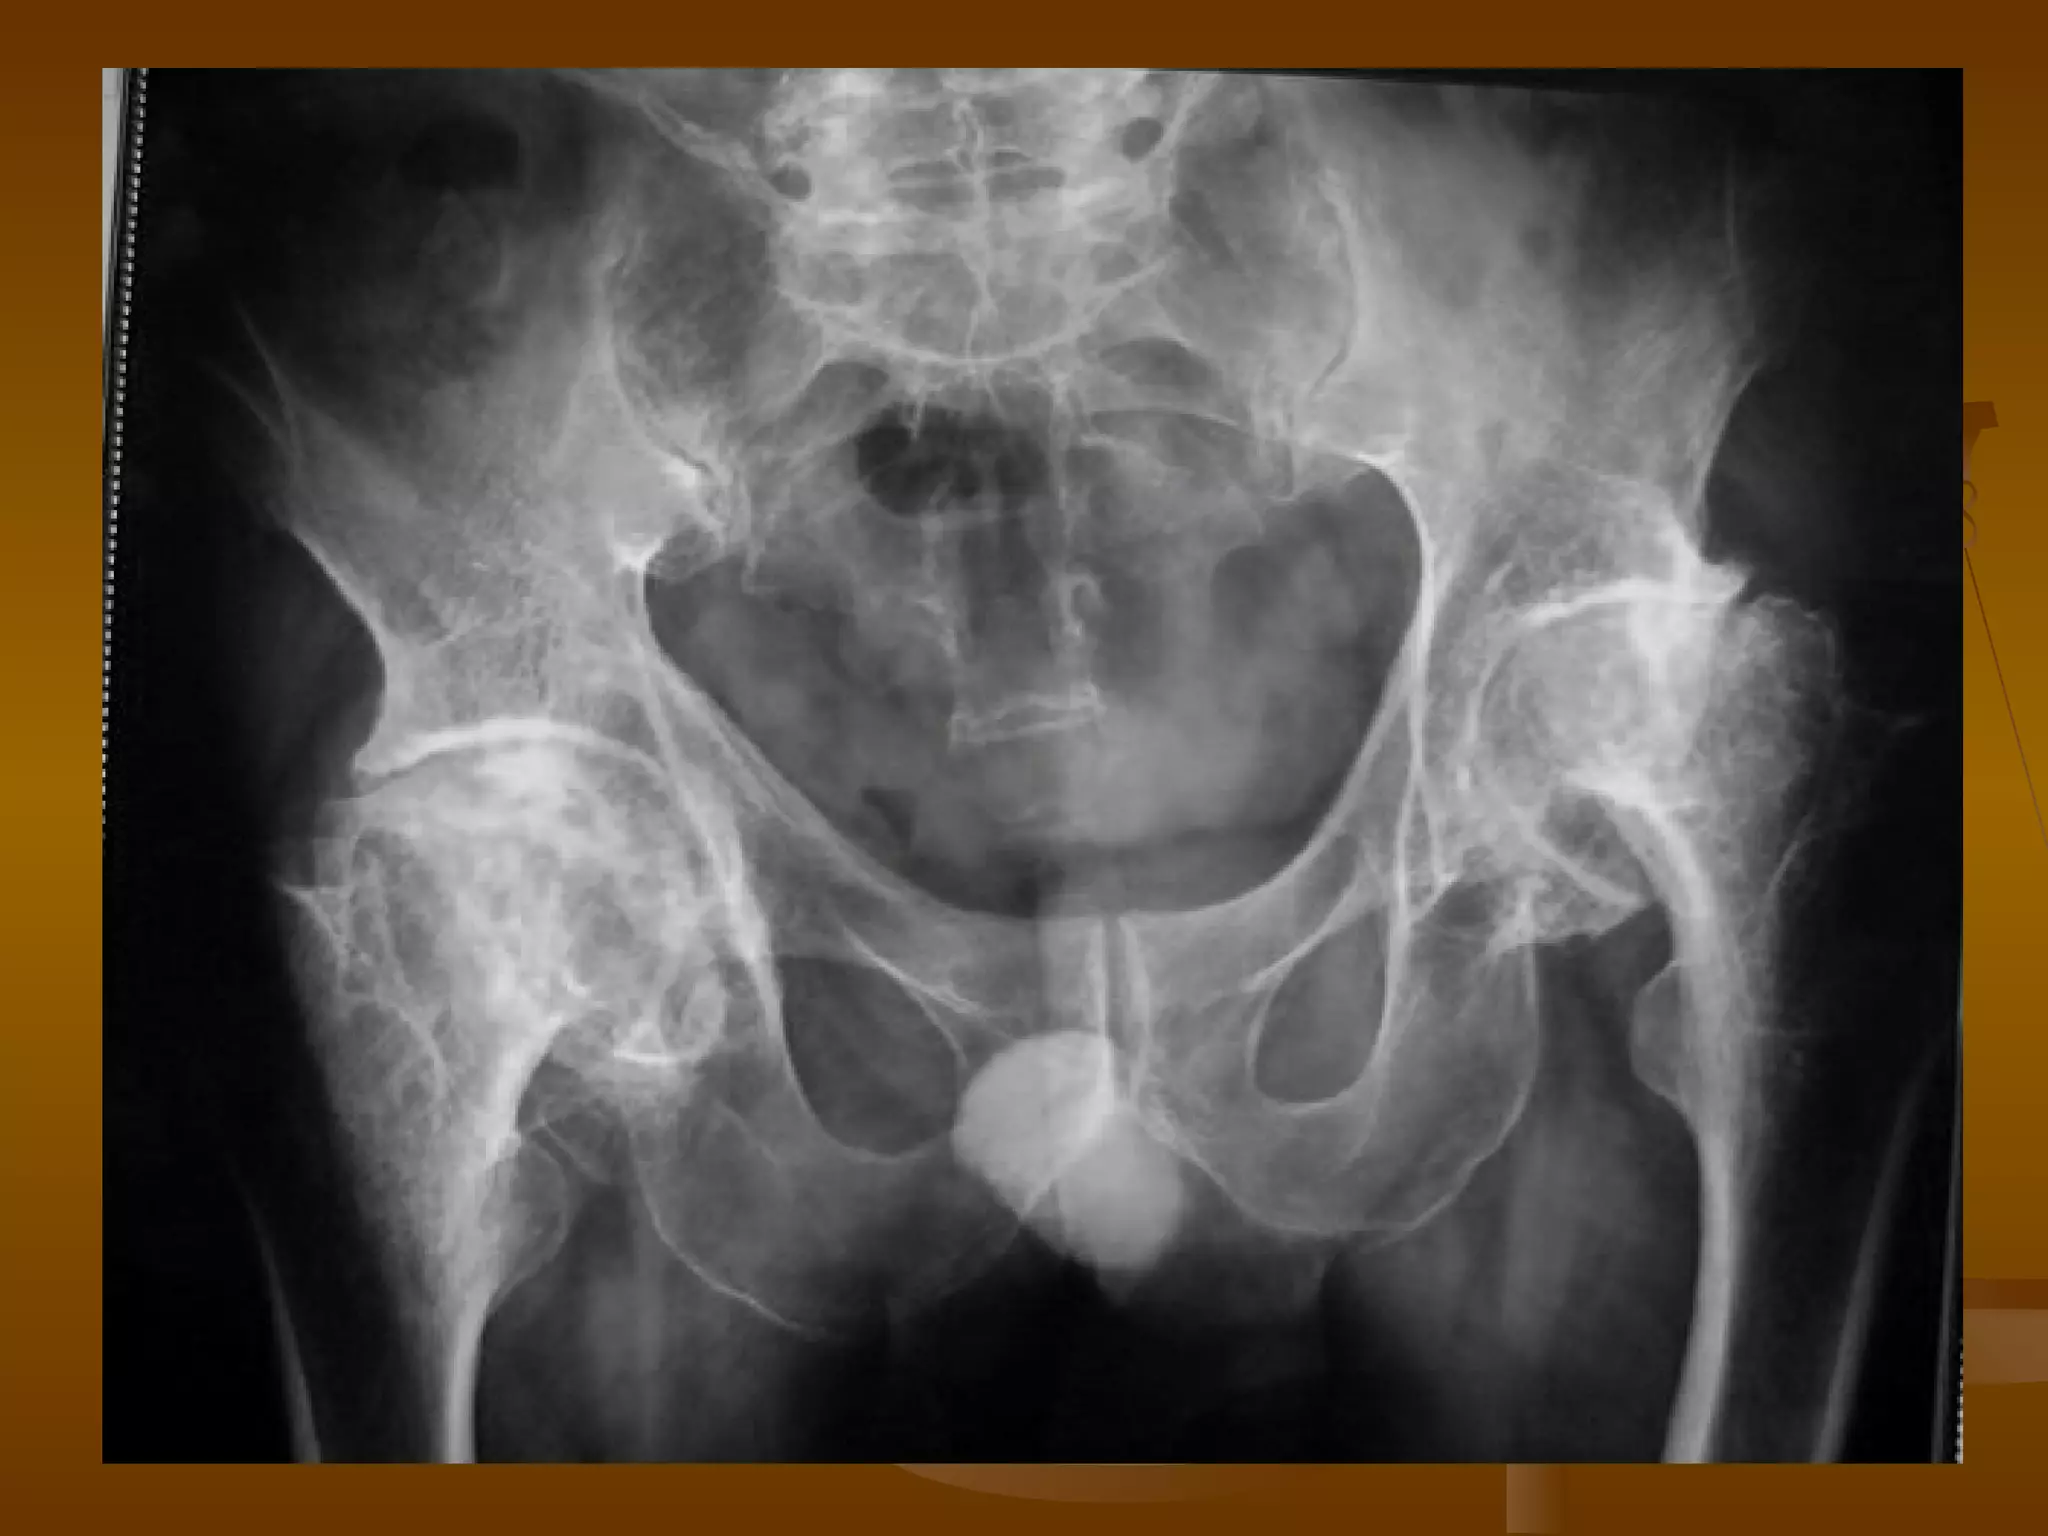

X 线诊断 X 光表现—晚期 股骨头明显变形、压缩、塌陷、骨密度不均匀。 病灶可累及整个股骨头,最终出现股头分节、碎裂。 并导致髋关节间隙狭窄和退行性骨关节炎。

CT 诊断   Ⅳ 期 股骨头增大变形、碎裂。 股骨头内骨质密度不均匀,累及整个股骨头,可见股骨头骨折。 关节间隙狭窄。 髋臼关节面受累,广泛增生、硬化、囊变,髋臼增宽变形。 盂唇骨化,出现退行骨关节炎。